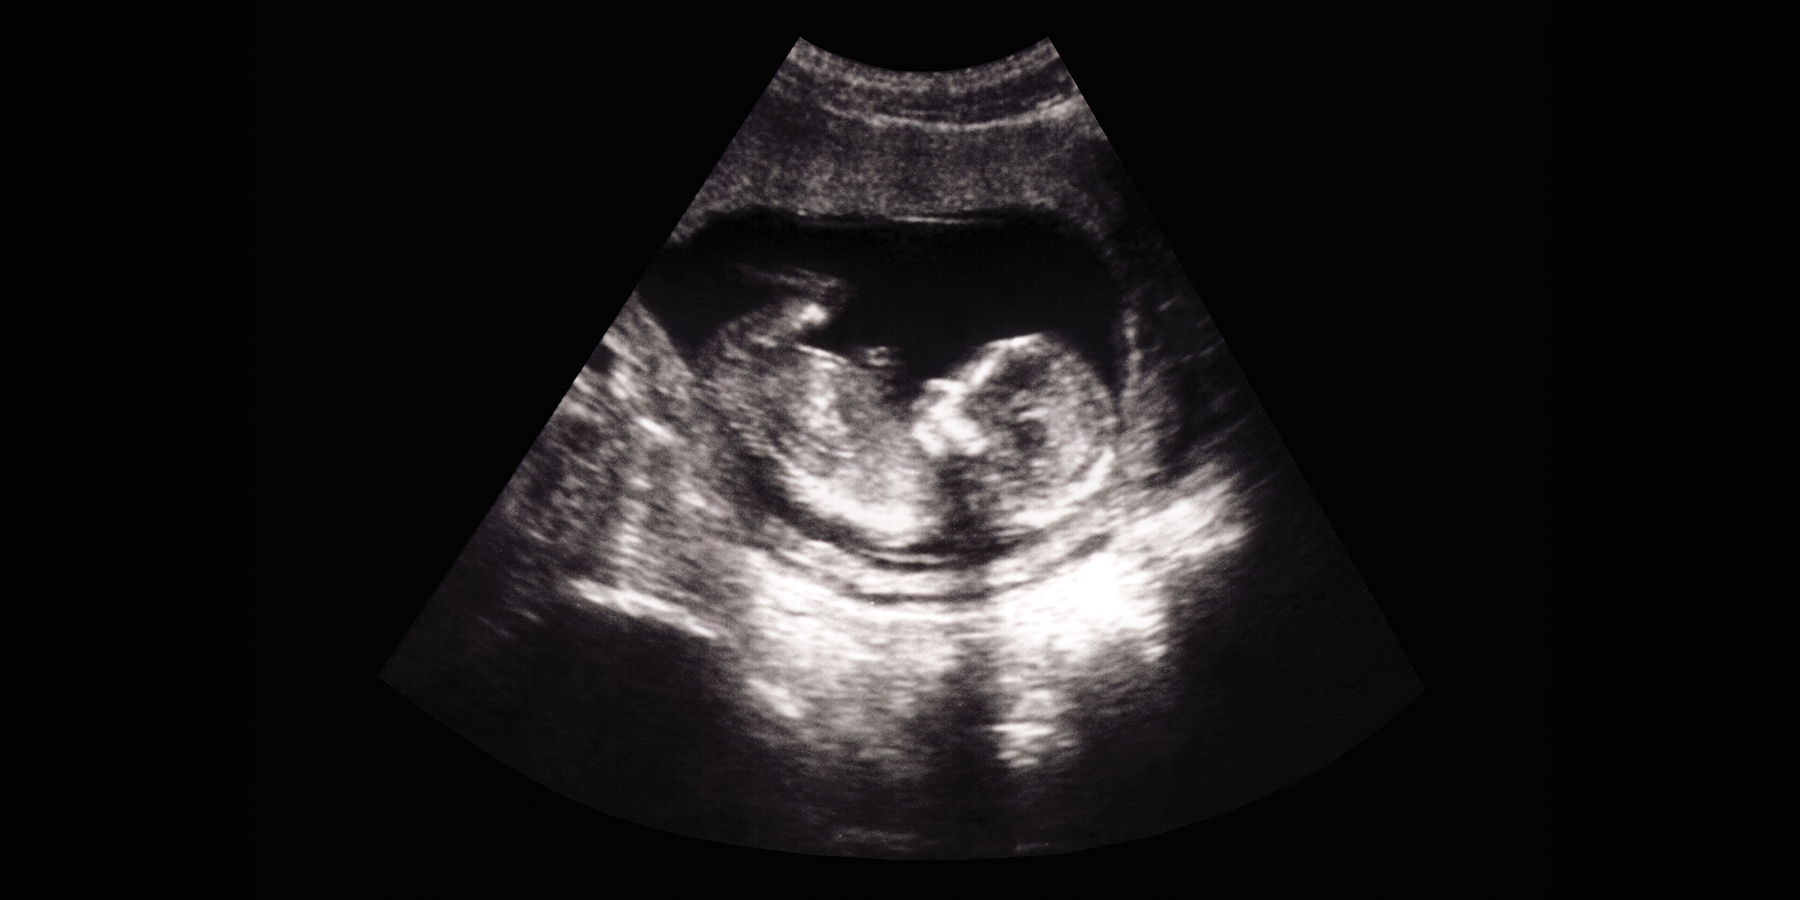

BIRMINGHAM, AL — The lungs and placentas of fetuses in the womb—as young as 11 weeks after conception—already show a bacterial microbiome signature, which suggests that bacteria may colonize the lungs well before birth. This first-time finding deepens the mystery of how the microbes or microbial products reach those organs before birth and what role they play in normal lung and immune system development.

A team led by University of Alabama at Birmingham researcher Charitharth Vivek Lal, MD, found that a human fetal microbiome DNA signature is present in lungs as early as the first trimester. This fetal lung microbiome showed changes in diversity during fetal development, suggesting microbiome maturation with advancing gestational age. Finally, a placental microbiome was also present in human fetal tissue, and this microbiome signature showed some taxonomic overlap with the corresponding human fetal lung microbiome.

In the new study, 31 samples of lung, placenta and intestine tissue from fetuses between 11 and 20 weeks of gestation were collected. Duplicate, independent tests done in labs at Lee Kong Chian School of Medicine, Nanyang Technological University, Singapore, and at UAB detected bacterial DNA in all samples. The two labs used different DNA extraction kits and different microbiome analysis pipelines.